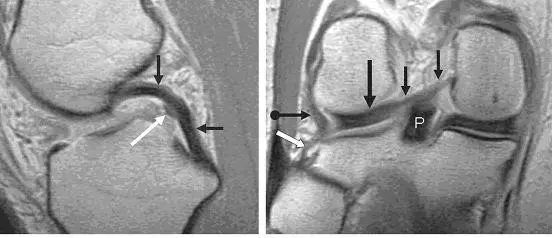

图 5 正常后交叉韧带和半月板股骨前后韧带

左图:经过后交叉韧带的矢状面,显示连续均质低信号的后交叉韧带(黑色箭头),其前方是半月板股骨前韧带(Humphry 韧带,白色箭头)。右图:冠状位片显示半月板股骨后韧带(Wrisberg 韧带,黑色短箭头不带圆点)从外侧半月板后角(黑色长直箭头)连接到股骨内侧髁外面。同时可见腘腓韧带(白色箭头)从腓骨头到腘肌腱(黑色短圆箭头),P 为后交叉韧带。